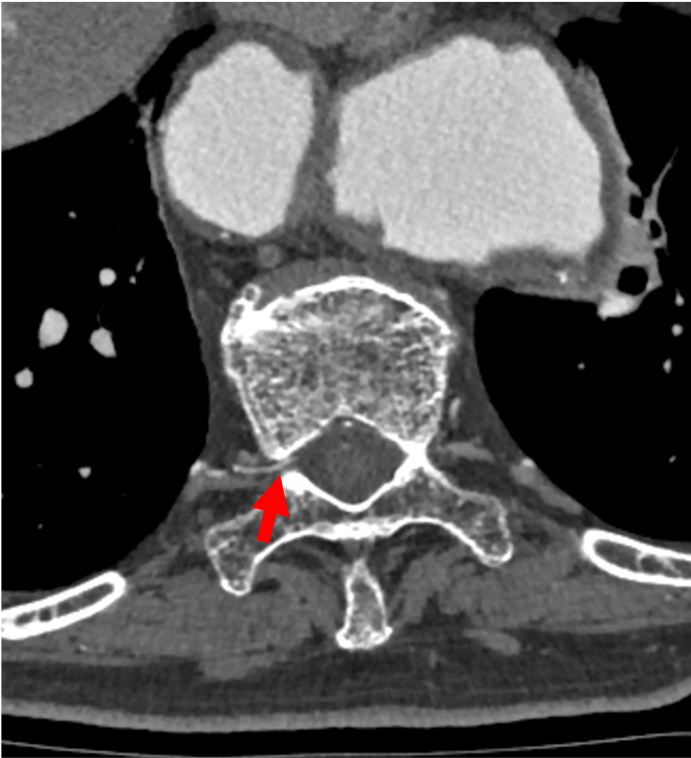

胸腹部大動脈瘤の術前検査として施行された。右第10肋間動脈から分岐し、脊柱管内右側を上行、ヘアピンカーブをなして前脊髄動脈に合流する動脈が描出され、アダムキュービッツ動脈と考えられた。

当該疾患の診断における造影CTの役割

アダムキュービッツ動脈は最も太い前根髄動脈を指し、肋間動脈や腰動脈から分岐しヘアピンカーブを描いて前脊髄動脈に合流する。第8肋間動脈から第1腰動脈から分岐することが多く、また左側から分岐することが多い。脊髄循環の維持を目的に、胸腹部大動脈瘤の術前においてはアダムキュービッツ動脈の同定が要求されることが多い。アダムキュービッツ動脈の同定においては、肋間動脈または腰動脈から分岐して脊柱管内を上行しヘアピンカーブを描いて前脊髄動脈に合流するという特徴的な形態をCT angiographyの元画像で丹念に探すことが重要である。Volume Rendering (VR) 像を作成すると全体を俯瞰できアダムキュービッツ動脈の走行の全体像を容易に認識することができる。